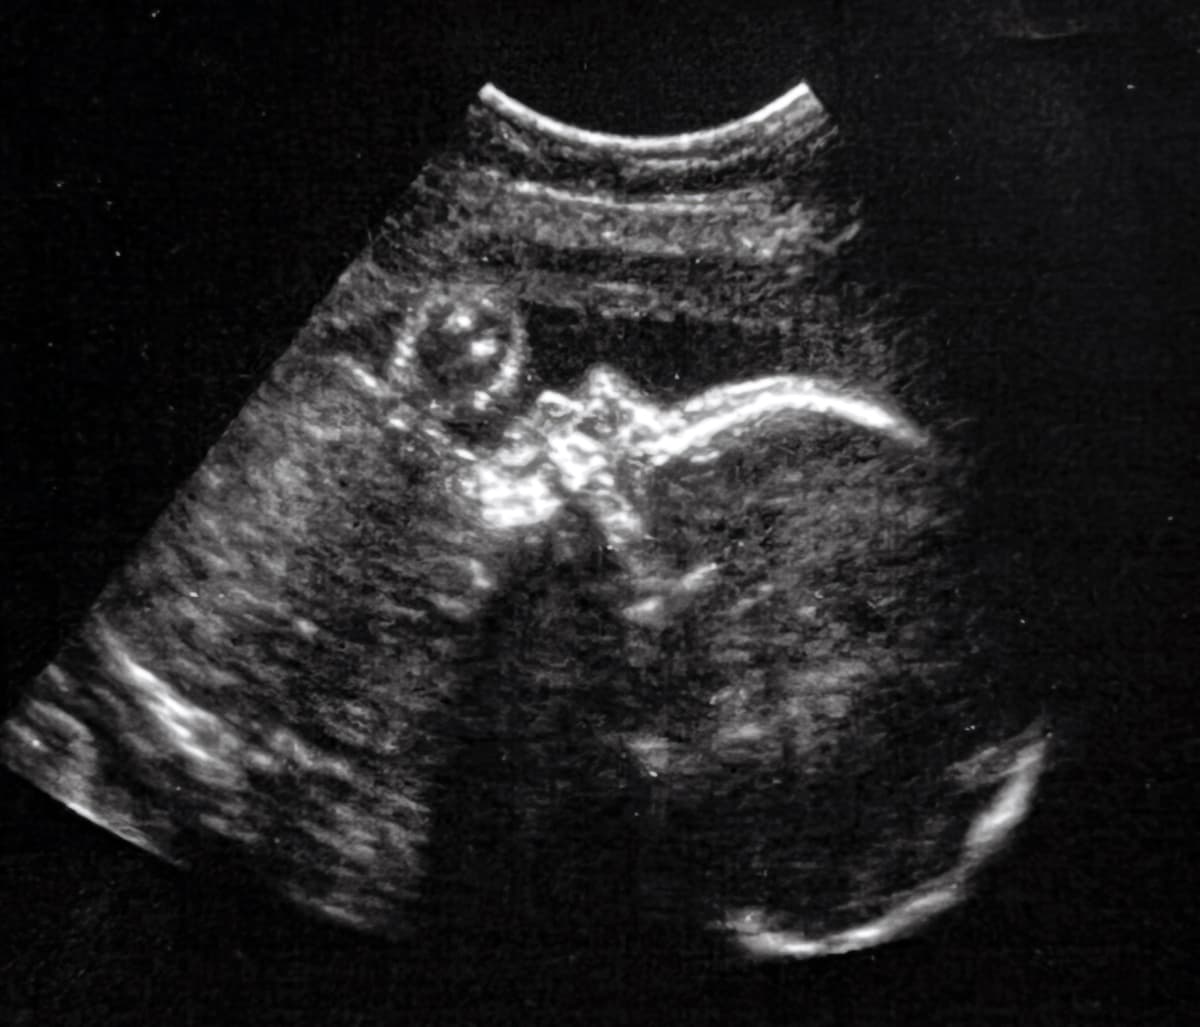

Με τη βοήθεια υπερήχων, οι χειρούργοι του Boston Children’s Hospital στις ΗΠΑ χρησιμοποίησαν μία νέα τεχνική για να αντιμετωπίσουν μία σπάνια προγεννητική ασθένεια, η οποία επιτρέπει στο αίμα να ρέει με επικίνδυνα υψηλές ταχύτητες στον εγκέφαλο μόλις το παιδί γεννηθεί. Αυτό επιβαρύνει την καρδιά και αυξάνει το ρίσκο για ανακοπή, προκαλεί υπέρταση και μπορεί να οδηγήσει σε νευρολογικές ή γνωσιακές διαταραχές, ενώ έχει και μεγάλο ποσοστό θνησιμότητας. Η επιτυχία της επέμβασης δίνει ελπίδα για την αντιμετώπιση της κατάστασης πριν να αυξηθεί το ρίσκο.

Η επέμβαση έλαβε χώρα όταν το έμβρυο ήταν 34 εβδομάδων στην κοιλιά της μητέρας του και οι γιατροί αναγκάστηκαν να προχωρήσουν σε υποβοηθούμενο τοκετό δύο μέρες αργότερα, επειδή η επέμβαση είχε σκίσει πρόωρα τις μεμβράνες της μήτρας. Ωστόσο, μόλις γεννήθηκε, το καρδιοναπνευστικό σύστημα λειτουργούσε σωστά και δε χρειάστηκαν περαιτέρω θεραπείες ή χειρουργεία. Απλά επειδή ήταν πρόωρος τοκετός, το βρέφος έμεινε αρκετές εβδομάδες στην εντατική θεραπεία για παρακολούθηση.